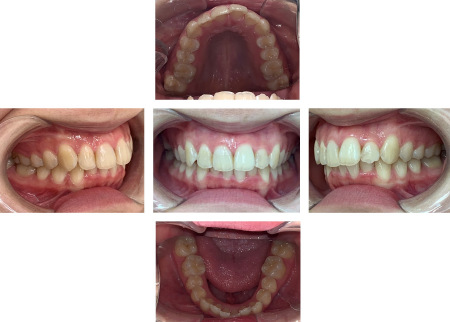

歯並びが改善し、見た目が良くなっただけでなく、前歯で物が噛みやすく歯磨きもしやすくなりました。

下顎の叢生が少し残りましたが、上顎はきれいに並びました。

患者様からは「以前の歯並びよりきれいになって嬉しい」とご満足いただけました。

現在、後戻りはなく定期検診にご通院いただき経過を観察しています。